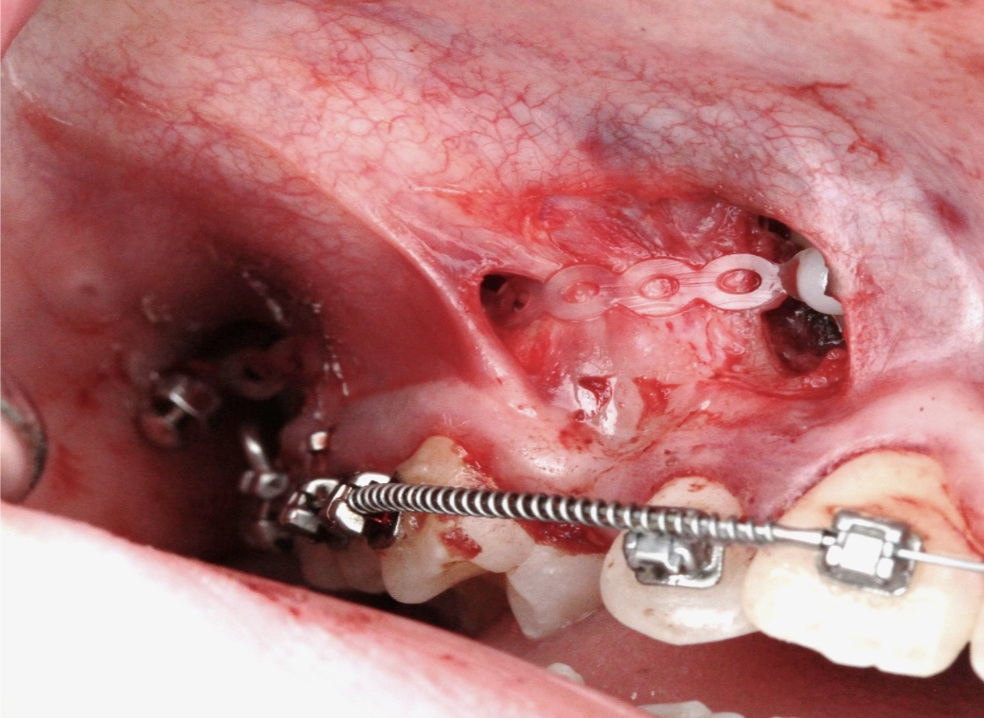

Мир мягких тканей в хирургической стоматологии

На курсе вы научитесь уменьшать негативные последствия хирургических вмешательств в полости рта и снижать риски осложнений.

День 2. Практическая часть на биофантомах

• Консервация лунки с помощью десневых трансплантатов (свободный десневой, VIP-CT).

• Ролл-техника для компенсации дефицита объема тканей в эстетической зоне.

• Упрощенный способ забора мягких тканей с бугра верхней челюсти.

• Мобилизация щечного лоскута различными способами.

• Небный скользящий лоскут.

• Рабочие швы для повседневной практики.

Вы научитесь

• Вести лунку удаленного зуба и управлять оро-антральным сообщением.

• Правильно выбирать и применять различные виды швов для достижения пассивного закрытия раны.

• Мобилизовать небный лоскут и компенсировать дефицит объема тканей в эстетической зоне с использованием ролл-техники.

• Извлекать мягкие ткани с бугра верхней челюсти и мобилизовать щечный лоскут различными способами.

• Выбирать тип швов подходящий для каждой клинической ситуации.

Фотогалерея